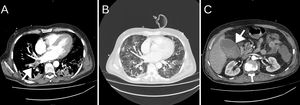

Treatment with enoxaparin 40mg every 12h was started after weighing up bleeding versus thrombotic risk due to PE. Bronchoalveolar aspirate (BAA) samples were taken for culture, being positive for Staphylococcus aureus and Proteus mirabilis, culture and auramine–rhodamine stain were negative for TB, and nasopharyngeal swab was negative for methicillin-resistant S. aureus (MRSA). Serum galactomannans were slightly positive, but fungal colonies were never isolated in respiratory specimen. Haemoptysis episodes persisted for 48h, so in consensus with the vascular and interventional radiologist diagnostic arteriography was performed.

The image showed hypertrophy of the bronchial arteries with pathological vascularization of the RLL (right intercostobronchial trunk and right branch of the bronchial trunk), so these were embolised without incident (Fig. 3). Haemoptysis improved and the patient was disconnected from mechanical ventilation 2 days later. He also developed acute kidney injury stage 2 with hypernatremia and hypokalaemia that progressively improved. Eight days after admission to the UCC, he was discharged to the Semicritical Pulmonology Care Unit.